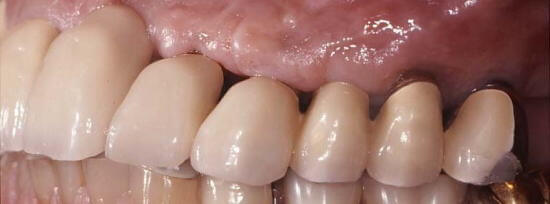

インプラント治療後6年経過した口腔内写真

インプラントを使用することにより、義歯を使わずに欠損を回復(6年経過)